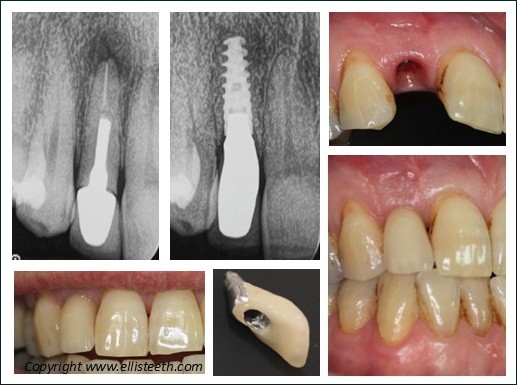

Implants

A dental implant is a titanium screw that fuses with the underlying bone.

A false tooth is attached to the implant once it has healed. This has aesthetic and functional advantages but most importantly is a stand-alone unit that does not involve the neighbouring teeth. Implants can also be used to stabilise loose dentures with studs or bars.

Implant restorations still need cleaning to ensure long term survival and, depending on the complexity, this can be time consuming.

Endodontics

This specialty refers to the removal of the nerve (pulp) of a tooth as is often called root canal (therapy). This is needed when the tooth dies and often causes a dental abscess directly from tooth decay or when teeth are heavily restored over the years.

Teeth will often need crowning afterwards to structurally reinforce them and prevent fractures. The restorability of the tooth/root is important to consider as part of the overall management process.

Restorative Dentistry is often destructive of tooth structure and will always need enhanced maintenance. Optimising tooth cleaning by the patient and professionally by the dental hygienist is essential. All restorations have a lifespan, also called longevity, and for veneers, crowns, bridges are considered as averages by scientific studies and in the order of 10-12-15 years with many caveats to these figures. The case below shows that sometimes there are different ways to achieve excellent results.